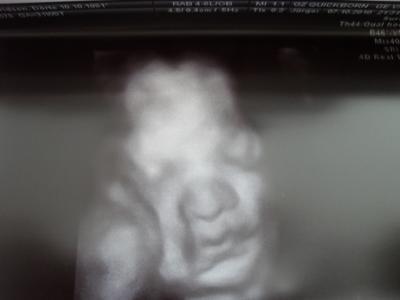

Anbei noch ein paar Bilder von unserer Kleinen. Sie wiegt übrigens 1600 g. Alles Andere erfahre ich Montag beim 3. Screening. LG - Dörte

Bild zu Die US Bilder zu der gestrigen 4D Sono - Forum für Dezember - Mamis